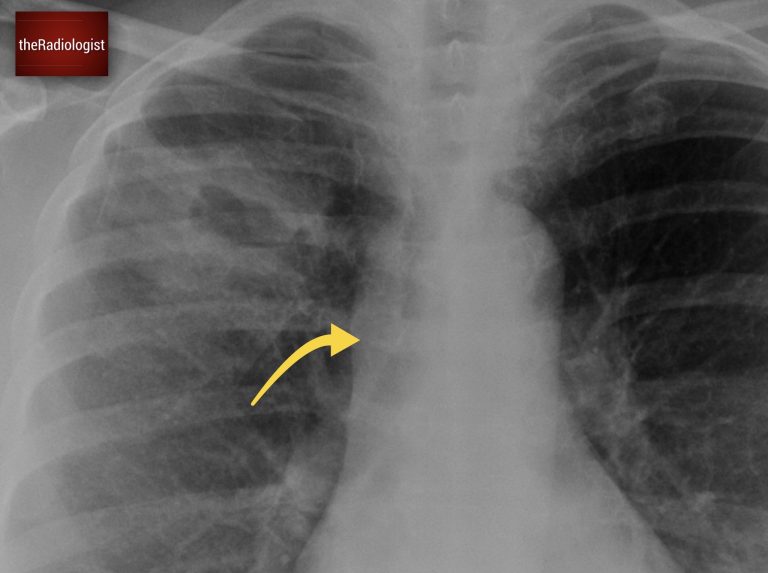

A woman in her 50s went to her GP with right-sided chest pain. Have a look at the initial chest X-Ray below:

PA Chest X-Ray

Have another look at the cavitating lesion. In this case, the lesion’s thick walls were a red flag, pointing towards malignancy. But this on its own wasn’t enough to confirm the diagnosis. There is however another sign on the film that is more specific.

See how the lesion in this case has a thick wall.

Now have a look on the right, outline all of these ribs and compare with the left. Any problems here?

If you look carefully, you will see the right ninth rib is missing. Now, this is significant. If there’s no history of surgery, the absence of a rib usually means it has been destroyed. And while infections like TB can sometimes cause partial erosion, complete rib destruction almost always points to lung cancer.

This time if you outline the right sided ribs and compare side by side you will find the ninth rib is missing.